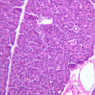

Although H & E staining permits ready identification of the islets of Langerhans, it does not permit differentiation of the various cell types that comprise the islets (B-36, H&E [10x, 20x, 40x-labeled]). There are no slides in the class collection that permit identification of all of the cell types of the endocrine pancreas. However, the sections on slides B-37 and B-40 permit specific identification of two cell types. Slide B-37 has been stained by the aldehyde fuchsin technique, which lends a magenta coloration to the granules of the insulin-producing B-cells. All other cells in the islets stain a dirty orange color (B-37 [10x, 20x, 40x] [10x, 20x, 40x]). Most of these orange-colored cells are the glucagon-secreting A-cells; however, you should bear in mind that somatostatin-secreting D-cells, as well as APUD cells that secrete pancreatic polypeptide are also scattered about the islet. The section on slide B-40 has been prepared by a silver impregnation method that renders some of the APUD cells in the islets (which appear as “clear cells” in ordinary preparations) dark brown or black (B-40 [10x, 20x, 40x]).